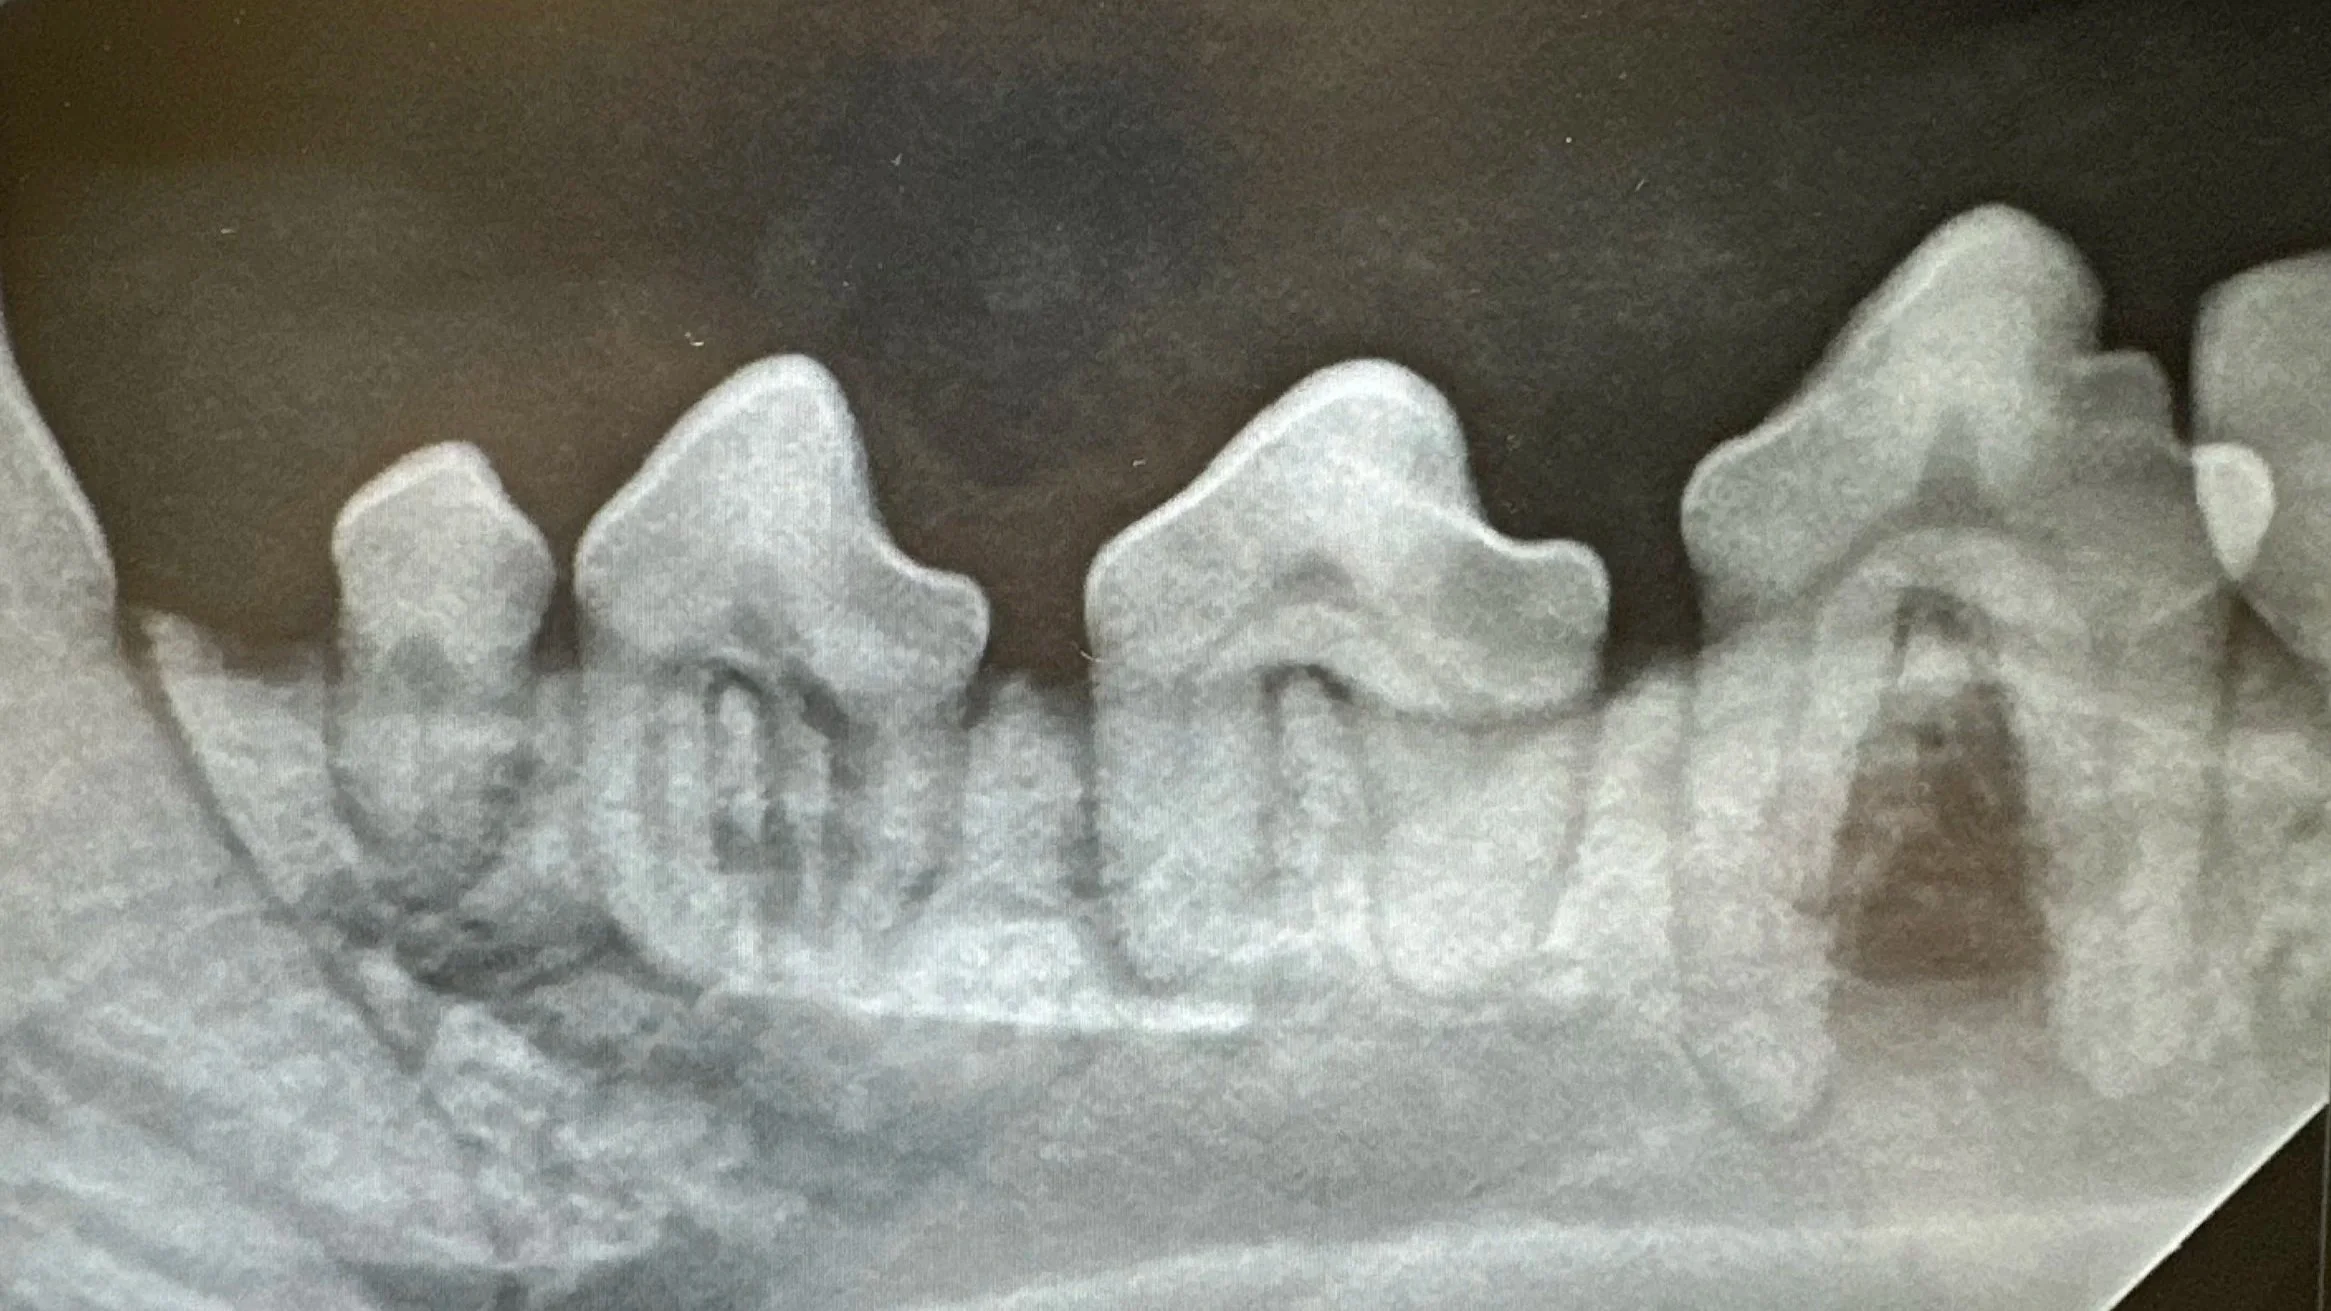

Dental imaging is one of the most important parts of a high-quality dental procedure. Much like an iceberg, the part of the tooth you see above the gum line is only a small fraction of the whole structure. The majority of disease—including infections, root resorption, and bone loss—hides below the gums where it cannot be seen with the naked eye. Without X-rays, this disease goes undetected and untreated, leaving pets in pain.

By using panoramic dental X-rays, we can quickly and safely detect hidden problems and provide the most complete, comfortable, and effective dental care for your pet.